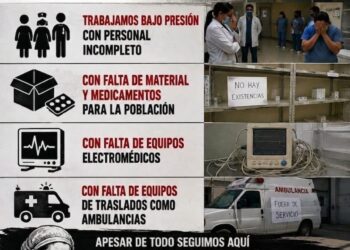

SIN HACER FIESTA

Fiel a su forma de comunicar, Rutilio Escandón anunció que esta semana llegarían las primeras vacunas contra el COVID19 a Chiapas, y así fue, anoche llegaron.

Como lo indica la estrategia, los primeros en ser vacunados serán los trabajadores de la salud, en especial quienes están en la primera línea de batalla.

Ello no quiere decir, por supuesto, que la pandemia ha concluido, sino al contrario…